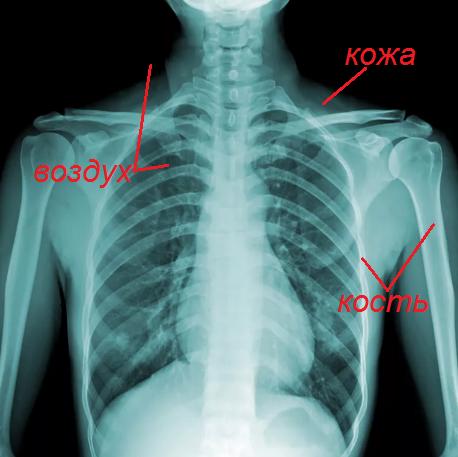

Если вы сейчас представите себе рентгеновский снимок, то сразу вспомните некий рисунок костей, которые можно увидеть как белые полосы. Кожу и органы также можно увидеть, но они уже будут менее интенсивно выражены, чем кости. Дело в том, что кости содержат кальций, который и задерживает эти лучи в организме.

Таким образом, можно заметить, что чем плотнее материал, тем светлее будет рисунок на плёнке. Кости видим белыми полосами, кожу сероватой, а воздух черным. Поэтому на картинке выше можно увидеть снимок грудной клетки, где внутри легких черный цвет - воздух.